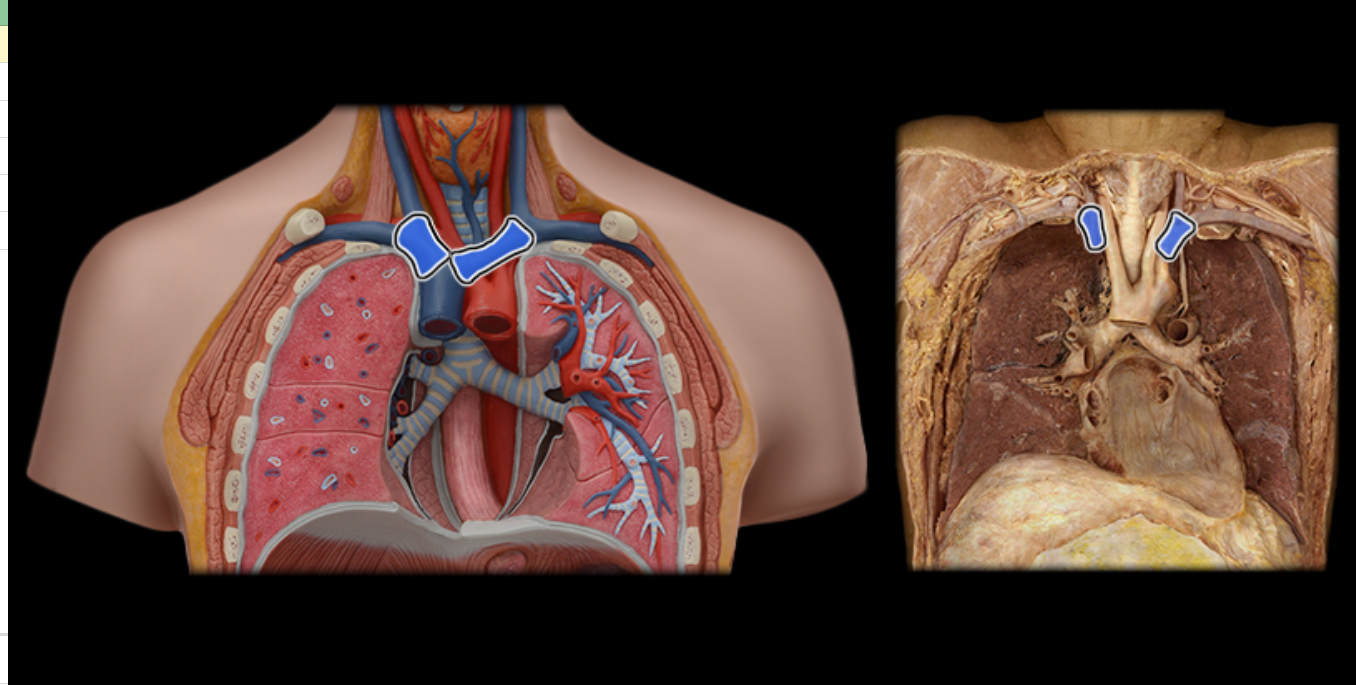

Brachiocephalic v.

Common carotid a.

Internal jugular v.

Pulmonary a.

Pulmonary vv.

Subclavian v.